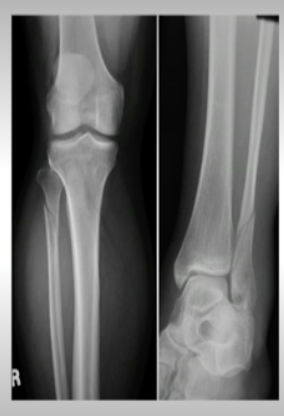

What is a Maisonneuve Fracture and what is the treatment?

Proximal fibula fracture + tear of medial ligament and syndesmosis (medial malleolus)

Tx: Long leg splint, NWB, ortho for ORIF